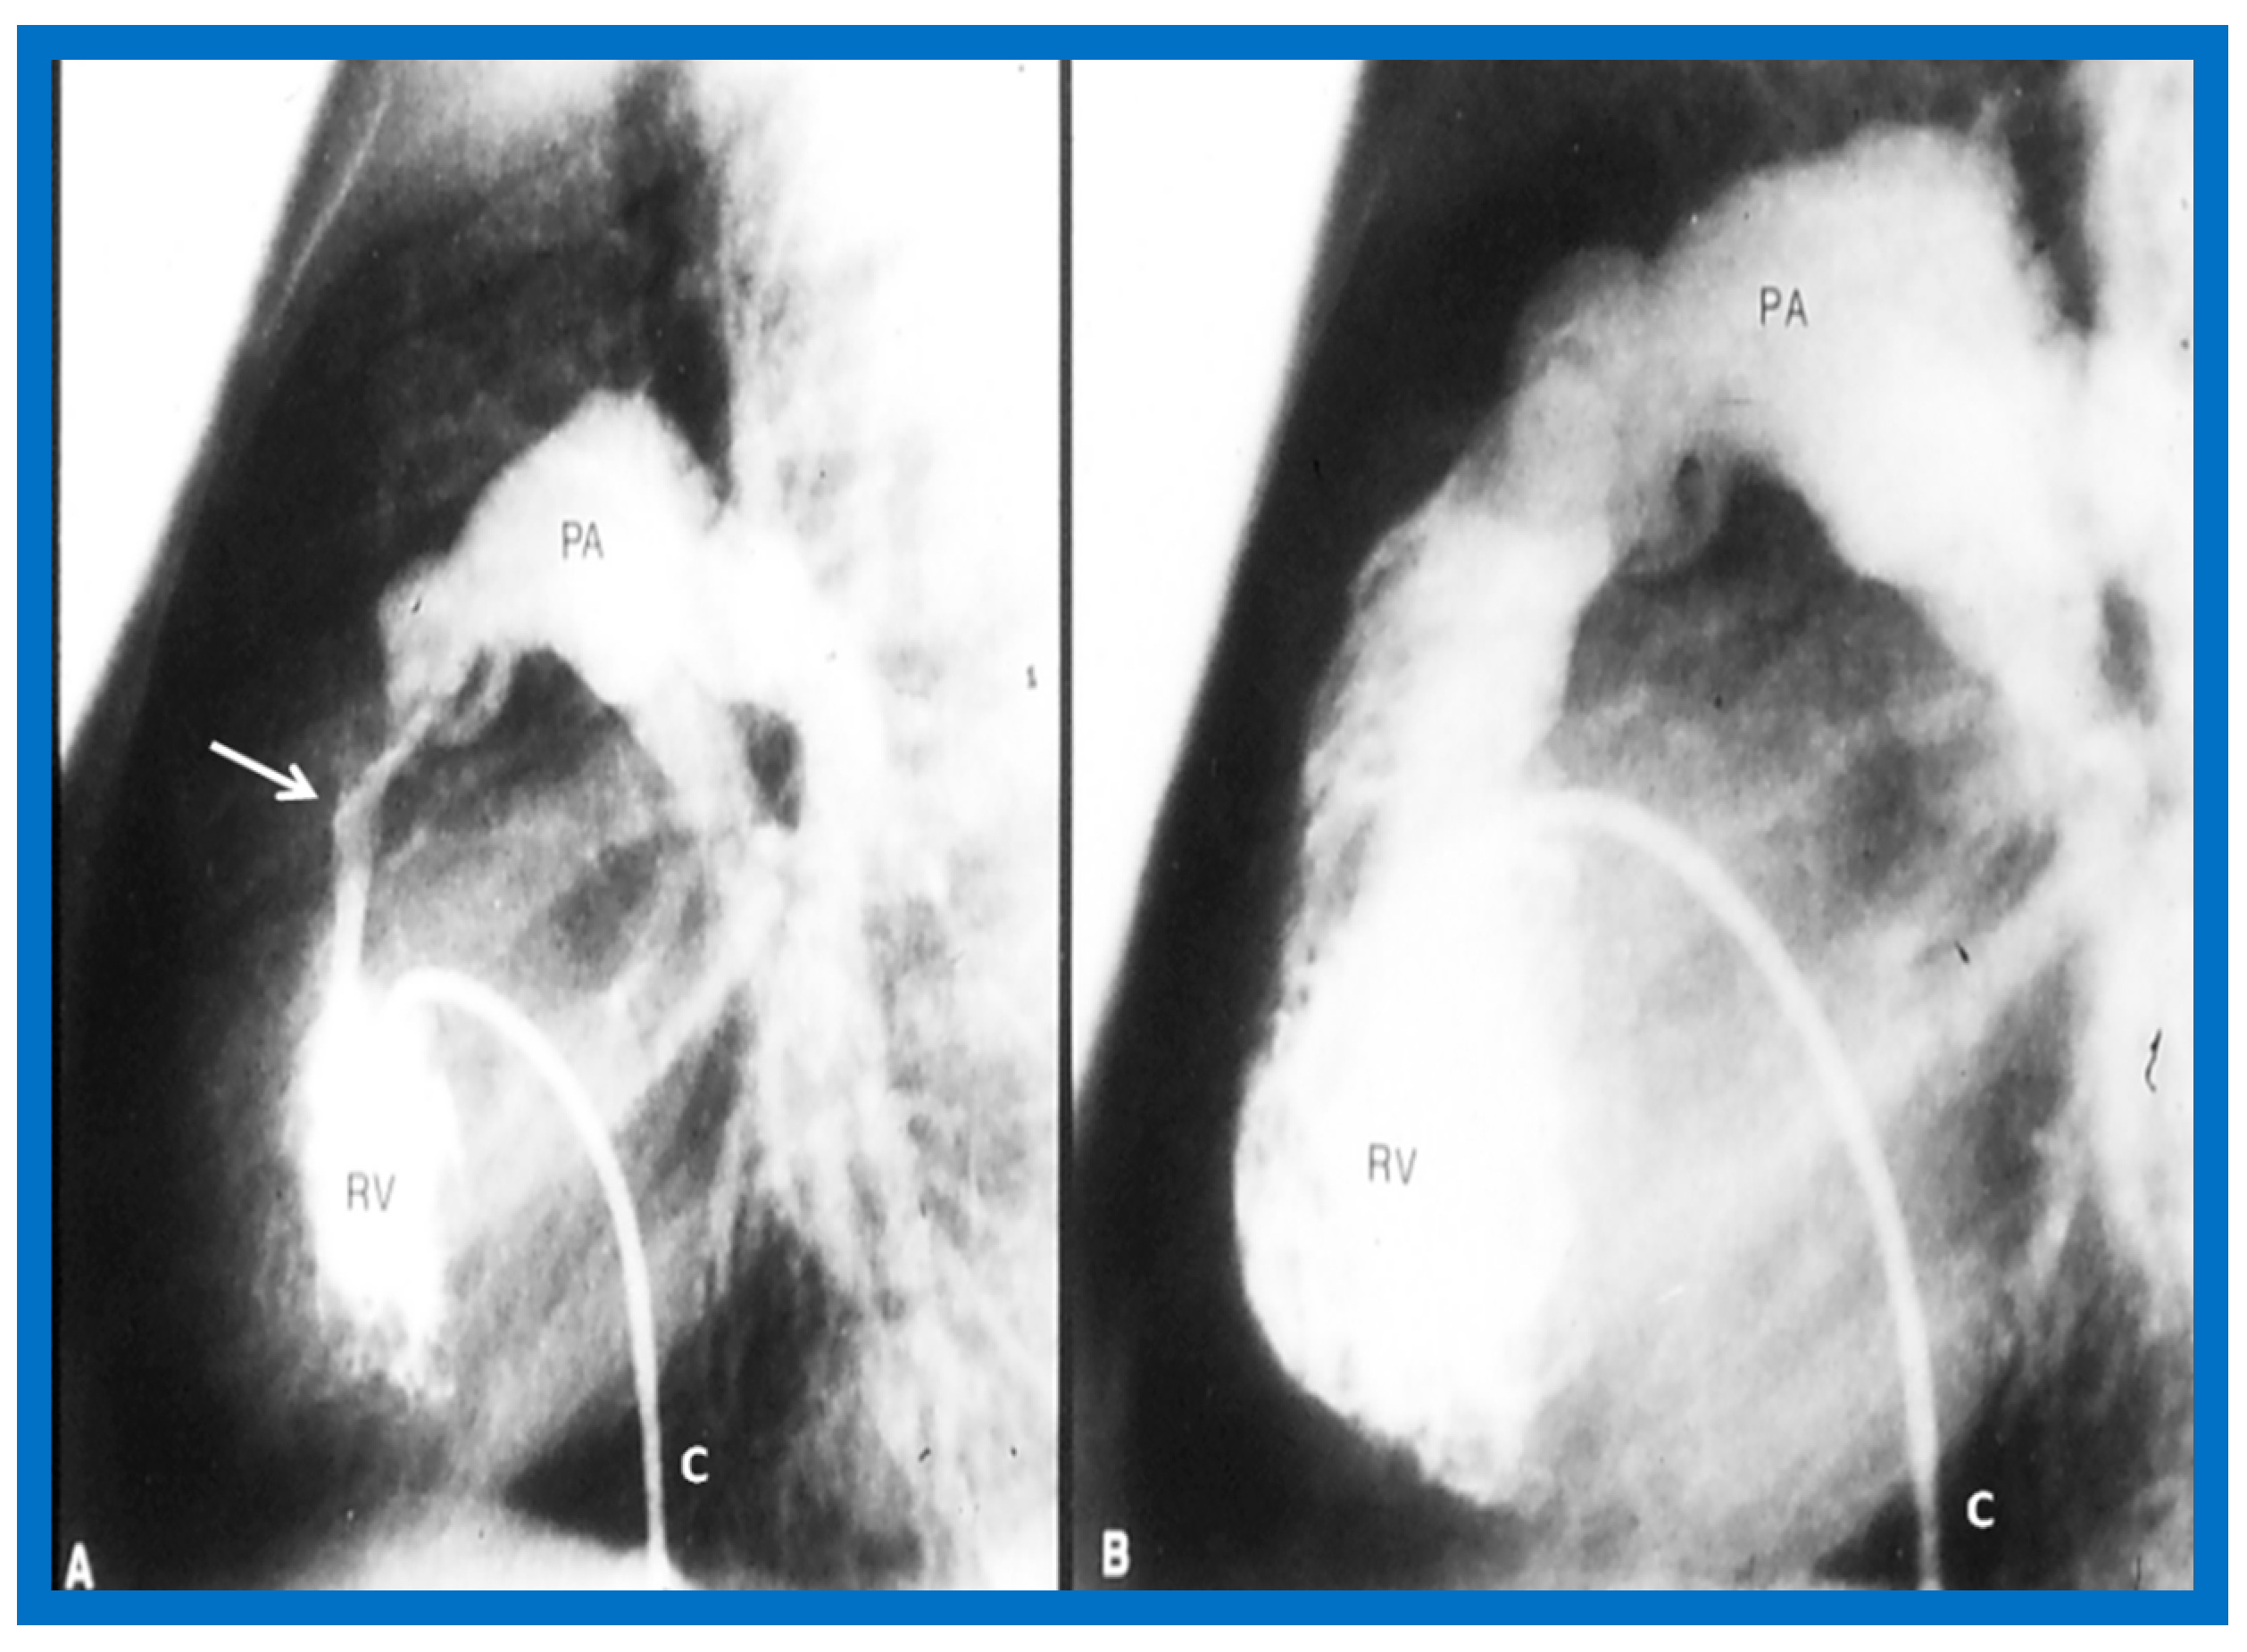

3.1. Pulmonary Stenosis

4.1. Pulmonary Stenosis

5.1.1. Causes of Restenosis